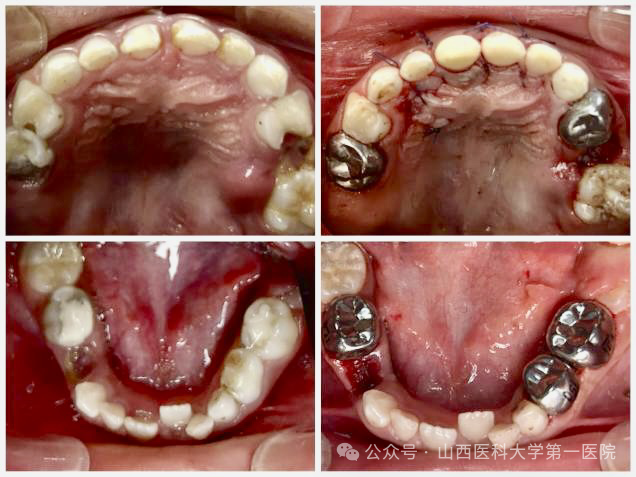

手术当天在麻醉科经鼻插管全气道管理全身麻醉下,口腔内科采用微创去腐复合树脂美学修复、牙髓根管治疗、牙髓切断术以及预成冠技术恢复患牙的形态及功能;口腔颌面外科团队微创拔除2颗埋伏牙多生牙,患儿术后2小时完全苏醒,经观察无任何不适于第二日上午离院。